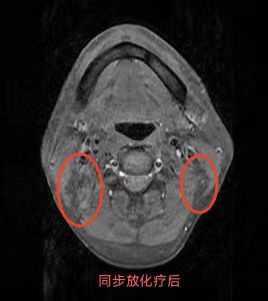

同步放化療(鼻咽癌伴頸部淋巴結轉移)